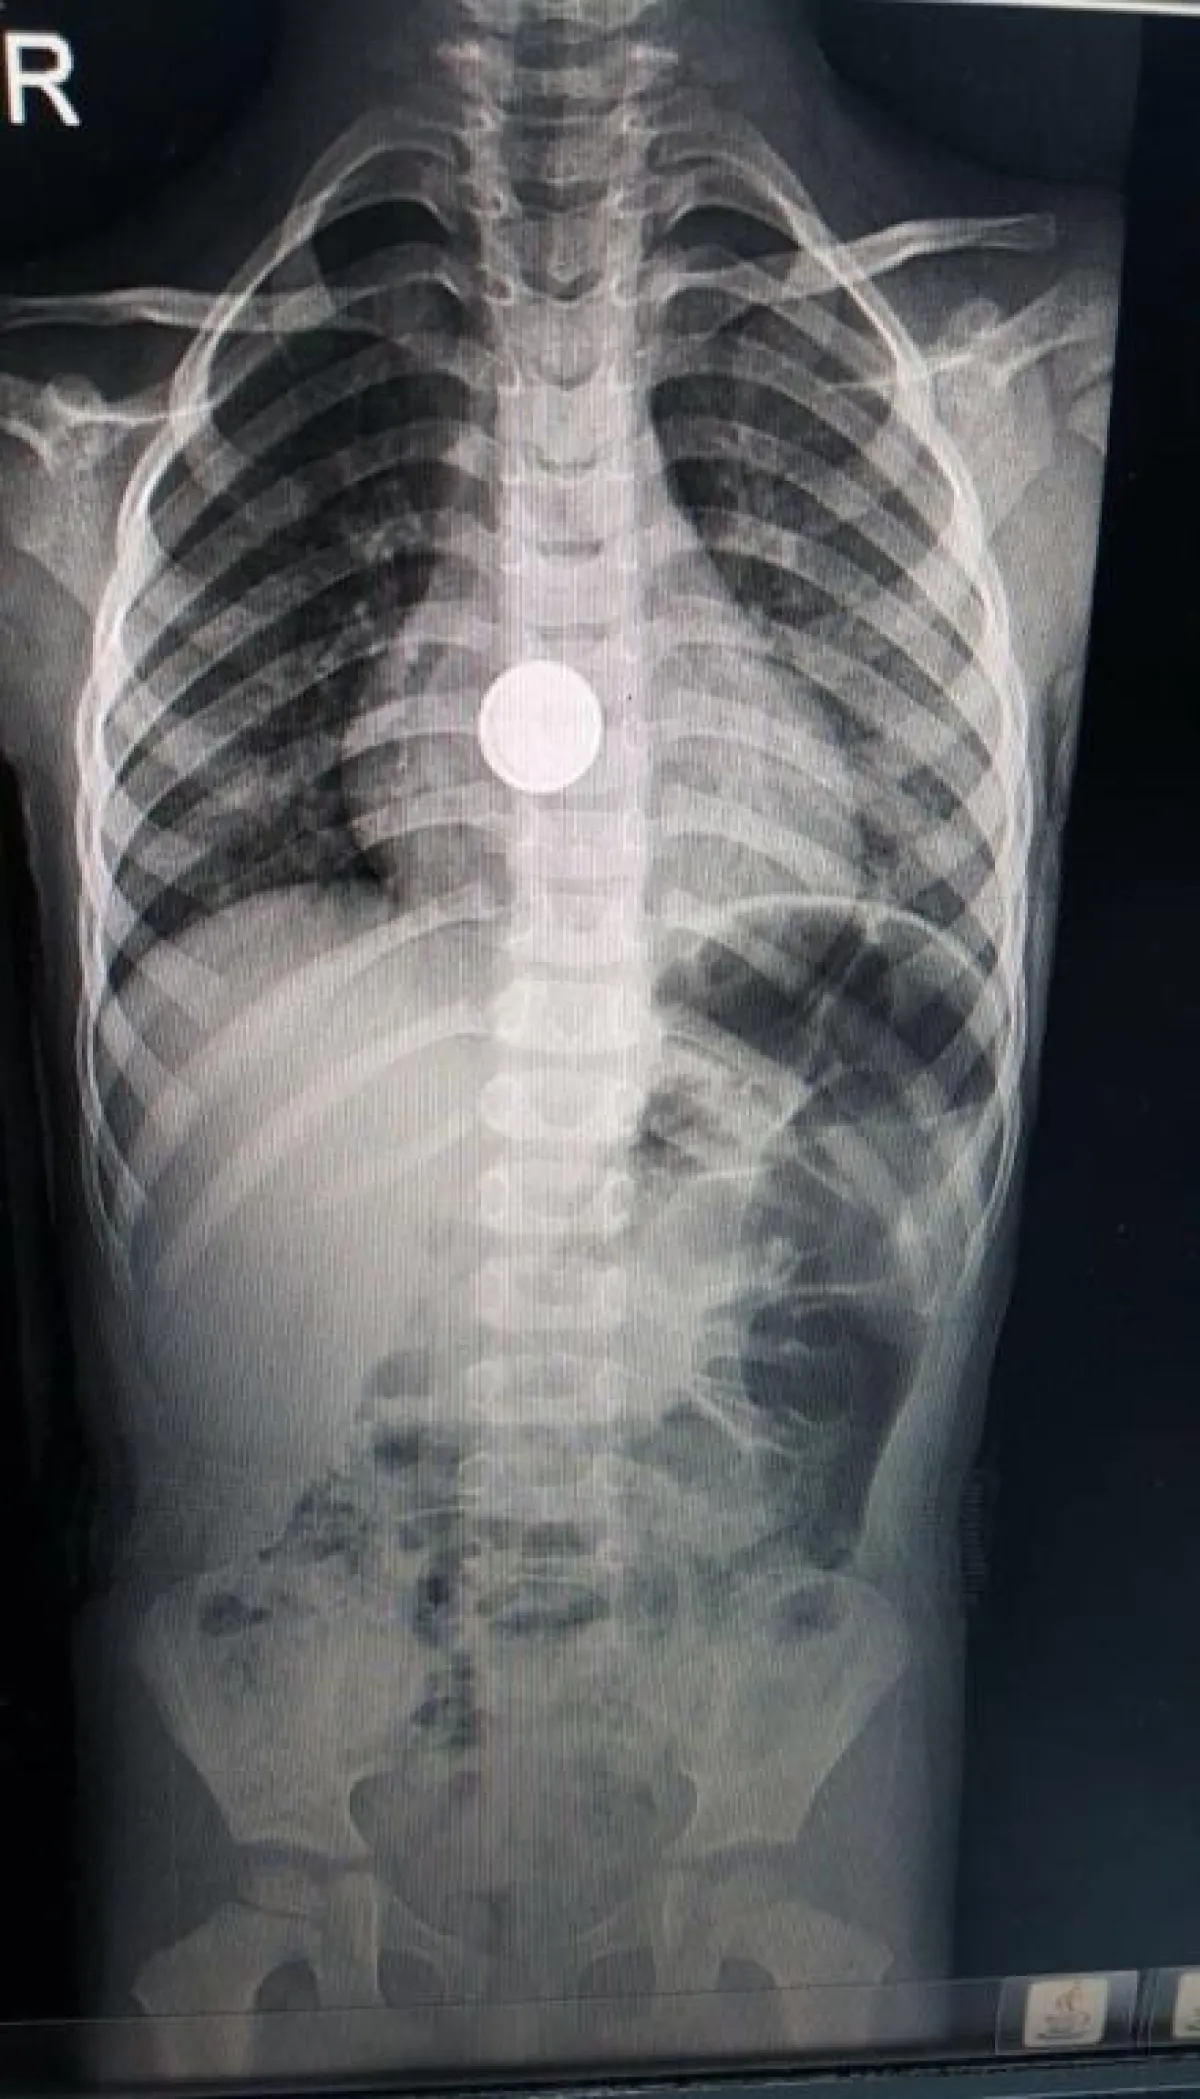

وعلى الفور تم قبول الحالة، وبعد عمل الأشعة في قسم الطوارئ اتضح أن الجسم الغريب هو عبارة عن بطارية قلوية وليس معدناً، وعالقة في وسط المريء، فجرى استخراج البطارية، وعمل اللازم خلال ٣ دقائق من الوصول إليها، ويخضع الطفل حالياً للعلاج في المستشفى ويتمتع بحالة طبية مستقرة، ولله الحمد.